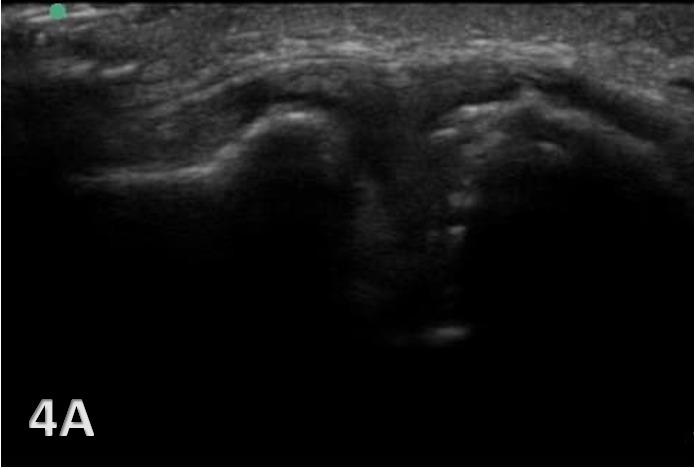

Sports physical therapists often deal with a range of musculoskeletal (MSK) issues, where accurate diagnosis and effective treatment are crucial for an athlete’s recovery and performance. The acromioclavicular joint (ACJ) plays a pivotal role in shoulder stability and movement, being the junction between the acromion process of the scapula and the clavicle. Given its importance, injuries to this joint, commonly resulting from falls, car accidents, or sports activities, can have significant repercussions. These injuries range from mild sprains, where ligaments are partially torn but the joint remains aligned, to severe dislocations with complete ligament tears and joint misalignment. Furthermore, repetitive use or wear and tear can lead to osteoarthritis of the ACJ, characterized by joint pain, stiffness, and swelling. Timely and accurate diagnosis is crucial for effective management. Traditional imaging techniques like radiographs often fall short in adequately assessing these injuries, particularly in visualizing soft tissues and dynamic joint function. MSK ultrasound has become increasingly popular for evaluating ACJ injuries, offering real-time, detailed imaging of soft tissue structures.

MSK ultrasound offers a non-invasive, cost-effective, and dynamic assessment of the ACJ. Its superiority in visualizing soft tissue structures, such as ligaments, articular cartilage, and the joint capsule, allows for a more nuanced diagnosis than what is achievable with radiographs. Its non-invasive nature also allows for repeated assessments, essential in monitoring the healing process or the progression of degenerative changes. This imaging modality is also beneficial for monitoring the healing process and guiding interventions such as injections.

In acute injury scenarios, MSK ultrasound effectively assesses the extent of ligament and soft tissue damage, aiding in the accurate classification or grading of the injury and facilitating appropriate treatment planning. In chronic conditions, MSK ultrasound aids in identifying degenerative joint changes due to repetitive use or aging. The ability to perform dynamic assessments with MSK ultrasound is particularly useful in evaluating joint stability and function. It also detects concomitant injuries like rotator cuff tears or fractures, often missed by radiographs. In chronic conditions, it helps identify structural changes within the joint due to repetitive stress or aging.